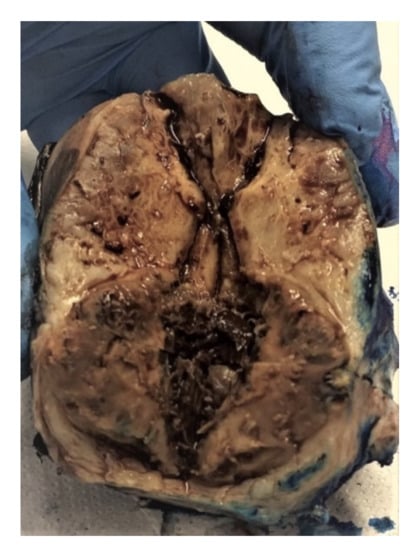

2.1. Dysgerminoma

2.1.1. Macroscopic Features